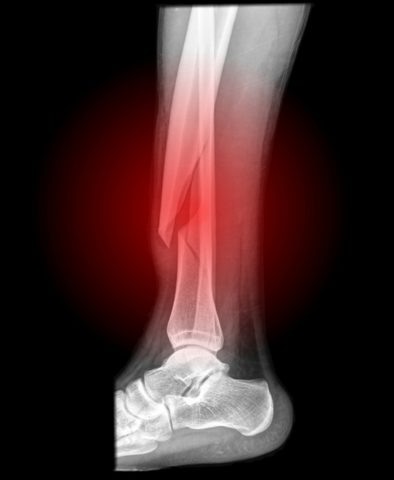

Повреждение костей голени.

На фото травма большой берцовой кости.